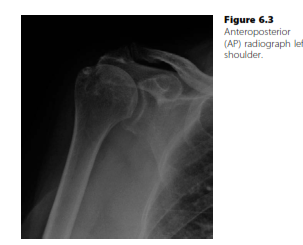

Shoulder and elbow structured oral examination question2 EXAMINER : Good afternoon. Can you tell me what is g…

Shoulder and elbow structured oral examination question5 EXAMINER : Good afternoon. Can you tell me the findi…